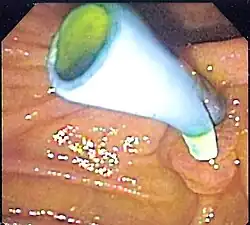

A colon stent is typically made of flexible metal mesh that can expand and hold open the blocked area, allowing for the passage of stool. Colon stents are used primarily as a palliative treatment for patients with advanced colorectal cancer who are not candidates for surgery. They help relieve symptoms such as abdominal pain, constipation, and bowel obstruction caused by tumors or strictures in the colon.

The placement of a colon stent involves endoscopic techniques similar to esophageal stenting. A thin tube called an endoscope is inserted into the rectum and guided through the colon to locate the blockage. Using fluoroscopy or endoscopic guidance, a guidewire is passed through the narrowed area and then removed after positioning it properly. The stent is then delivered over the guidewire and expanded to keep open the obstructed section of the colon. Complications associated with colon stents include perforation of the intestinal wall, migration or dislodgment of the stent, bleeding, infection at insertion site, or tissue overgrowth around it.[10]

Colon stenting provides several benefits including prompt relief from bowel obstruction symptoms without invasive surgery in many cases. It allows for faster recovery time compared to surgical interventions while providing palliative care for patients with advanced colorectal cancer by improving quality of life and enabling better nutritional intake. However, there are potential risks associated with complications such as migration or obstruction that may require additional procedures or interventions to address these issues effectively.[11]